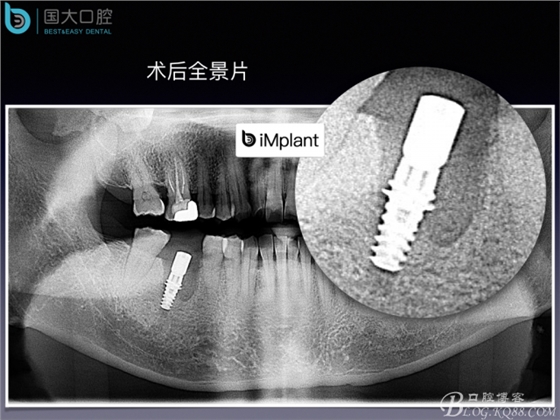

頰側骨壁嚴重缺失,應該如何設計種植位點?